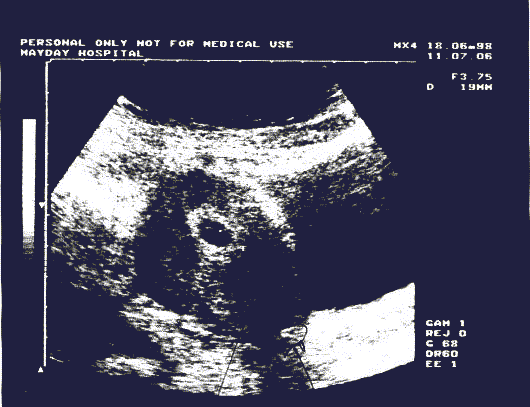

However that is not the end of the story, Tracey had another miscarriage in June 1998. The scan shown below was taken at the Mayday Hospital in Croydon in June of this year:

Ultrasound of implant

Please take note of the two foreign objects. This miscarriage was caused by. You and I both know that Tracey will never carry another healthy pregnancy. Yourself and the other specialists know the real cause of all her problems. It is the foreign objects that I have pointed out in the scans. My god sir, she has a 5 year old child, she has a right to know what is going on. I want to know what is going on as well. More importantly I want to know how these things got inside her. I am a reasonable person, but I will inform you that I have felt the need to go International on this. Those scans have been transmitted to doctors and Journalists all over the world. British Journalists are now showing an interest. I will be honest and let you know that the failure of the medical profession to remove these things will cost them dearly. You have no idea what it is like for her, the constant torture and the constant pain and discomfort.